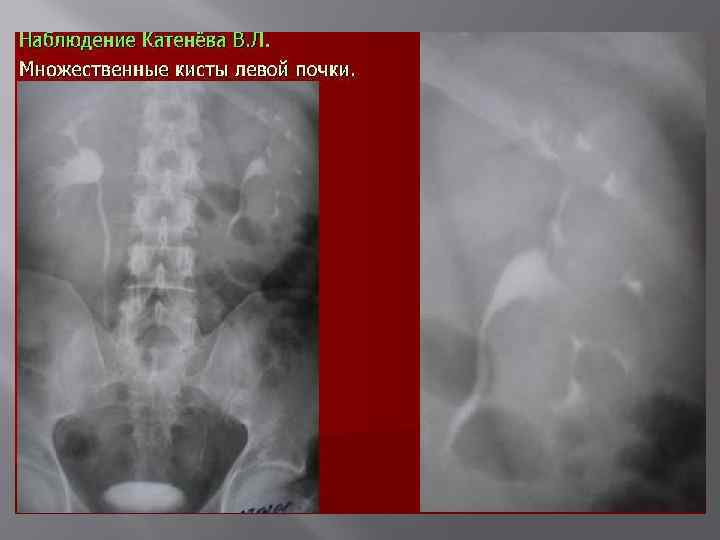

3. Структуры Поликистоз Солитарные кисты 4. Мочеточника Ахалязия Уретероцеле Ретроковальный

Поликистоз почек